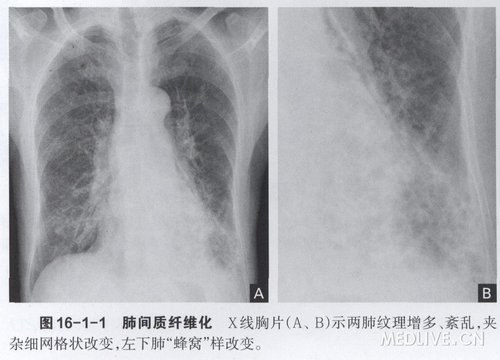

高清双肺间质性纤维化图_最新双肺间质性纤维